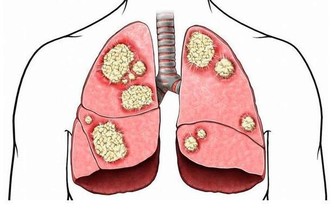

有脂毒的人一般偏胖、脂肪較多,經常喝酒、吃肉、吃油炸食品,對肝臟傷害很大,易得脂肪肝等疾病。想清除脂毒,首先要降血脂,建議用山楂、荷葉煮水喝,可化痰降脂;平時應多吃洋蔥等蔬菜;還可按揉小腿上的豐隆穴(位於外踝尖上8寸,條口穴外,距脛骨前緣二橫指處),可以消食導滯,減少脂肪。 5、瘀毒 瘀毒是指藏在血液里的毒,大多是從中年開始出現的,一般表現為舌下脈絡發紫、容易健忘、皮膚乾燥、胸悶憋氣、臉色暗等。有瘀毒的人,也可以用丹參或山楂泡水喝,可以活血化瘀,清除血管垃圾。 6、氣毒 氣毒是存在肺裡面的毒,中醫認為「肺主氣」、「腎主納氣」,有氣毒的人往往肺腎功能不好,一般身上氣味大,如有口臭、汗臭等。為了防止氣毒,可以每天早起做深呼吸,即「呼吸吐納」,把肺中的濁氣排出來,保持體內空氣的新鮮。

值得提出的是,肝是人體最大的排毒工廠,想要祛除毒素,要從根本上保肝養肝,使之能解毒排毒。建議經常用枸杞、菊花泡水喝,多吃桑葚,以及各類新鮮蔬菜。 日常生活中如何排毒 可別小瞧了這六種陰毒,如果這些毒素在我們的體內越積越多,那麼就會引起各種身體疾病,加速人的衰老。肝臟、腎臟和肺部是身體中最大的解毒器官,要想徹底排出身體的毒素,必須要保養好這些器官。除了上述排毒方法,在日常生活中應該如何排毒呢? 1、定時排便 便秘的滋味確實不好受,長期便秘也會讓我們的腸道積累大量的毒素,引起各種身體疾病。生活中我們除了要注意健康均衡的飲食外,還要養成定時排便的好習慣。無論身體有沒有便意,早上起床後都可以到馬桶上坐一會兒,培養自己的便意。時間長了,這樣就可以養成晨起排便的習慣。 想要定時排便,還可以按摩身體上的「排便穴」。這個穴位位於食指關節的尺側凹陷處,只要按摩一兩分鐘,身體就會產生強烈的便意。 2、堅持運動 現在很多人每天都忙於工作和應酬,很難抽出時間來運動健身。其實,要是能堅持每天都鍛鍊身體,這樣也可以幫助我們輕鬆排除體內的毒素。 比如:跑步、游泳和瑜伽等等。經常運動可以增強人的心肺功能,還能夠促進體內的血液循環。如果在運動過程中適量地補充一些水分,還可以加速身體排出毒素。 3、多吃素 我們每天都要攝入大量的食物,食物進入腸道後,一般要停留兩三天的時間。如果攝取過多的高糖、高脂肪和高膽固醇的食物,那麼身體就不容易消化,產生宿便。宿便對身體的危害非常大,可以使毒素在腸道中被二次吸收。 要想身體不積累毒素,可以多吃點素,少吃點葷腥。可以在一個星期當中選擇一天專門吃素食,這樣可以幫助我們清理腸胃。平時可以多吃點新鮮的瓜果蔬菜,因為這些食物中富含纖維素,可以促進人的腸胃蠕動,幫助身體把宿便排出去。 4、保持好心情 現在人們的生活節奏越來越快,工作壓力也比較大。如果長期處於精神緊張的狀態,就會影響五臟六腑的正常運行。很多時候我們生病都是因為工作壓力大和精神緊張導致的,因此,大家要放慢生活節奏,保持愉悅輕鬆的心情。 5、不熬夜 都說熬夜就是慢性自殺,熬夜對人體健康的傷害特別大。在晚上,身體的大部分器官都會進行排毒工作。如果晚上不睡覺,那麼排毒器官就會罷工。長期熬夜就會導致分泌系統紊亂,新陳代謝功能出現障礙,身體也會產生各種各樣的毒素。要想徹底排除體內的這些毒素,就要養成良好的作息習慣,保證充足的睡眠,儘量不要熬夜。 健康養生的第一步,讓我們排出毒素開始吧! -